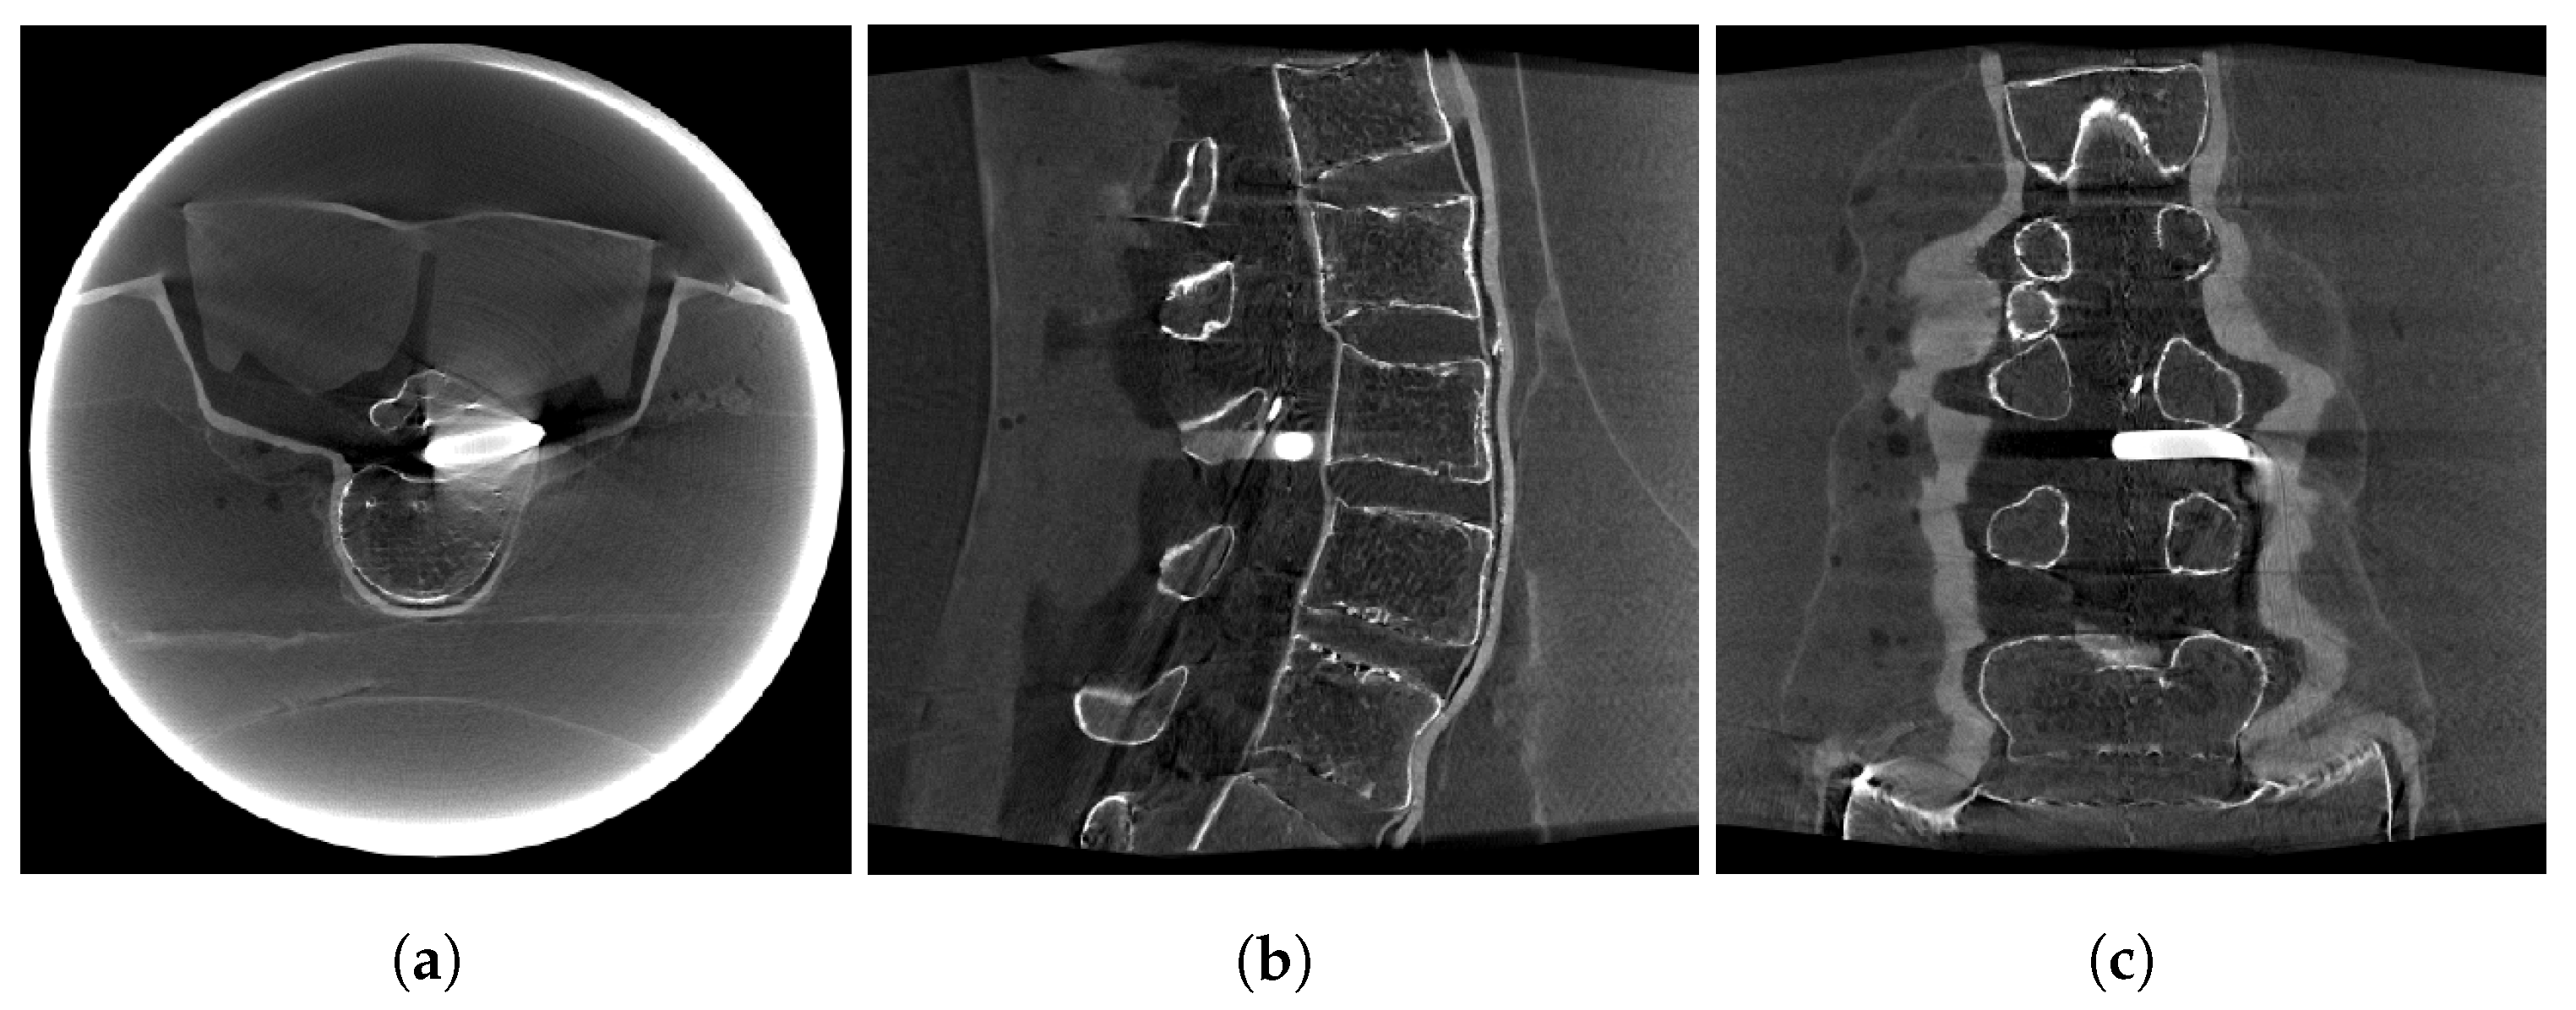

2.4. Image Data

3. Results